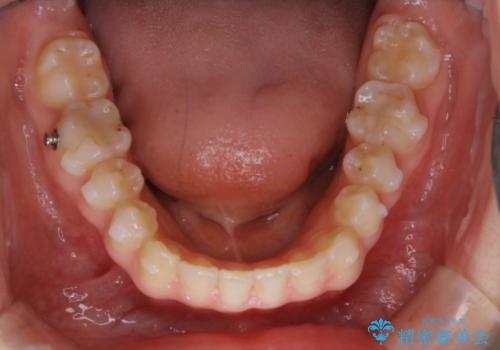

一見前歯のがたつきだけ改善させれば良い様に見えますが、このがたつきの原因は奥歯の嚙み合わせのズレからくるものであったため、インビザラインFULLで噛み合わせの改善から行っていきました。前歯の角度も改善されたために頑張って唇を閉じる必要がなくなり、横顔のシルエットも綺麗になりました。

前歯のがたつきだけを治そうとした場合、噛み合わせは二の次なってしまう事が多く、せっかく綺麗になった歯並びも後戻りしやすくなります。奥歯の噛み合わせからしっかり機能させることで、長期間にわたって綺麗な歯並びを保ちやすくなります。

インビザライン20時間以上正しく装着していただいたおかげもあり、短期間で治療することが出来ました。